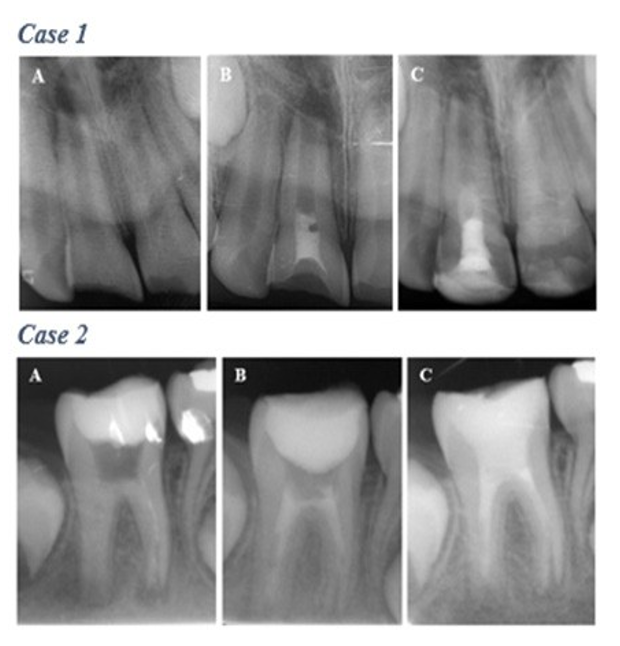

Figure 1. Complete healing category. Case 1. Maxillary right central incisor. Increased thickening of the canal walls and continued root maturation after revascularization; (A) Preoperative radiography. (B) Postoperative radiography. (C) Follow-up radiograph at 24 months. Case 2. Mandibular right first molar; (A) Preoperative radiography. (B) Follow-up radiograph at 24 months. Case 3. Mandibular right first molar; (A) Preoperative radiography. (B) Postoperative radiography. (C) Follow-up radiograph at 24 months. Case 4. Mandibular right first molar. (A) Preoperative radiography. (B) Follow-up radiograph at 24 months

Figure 2. Incomplete healing category. Case 1. Maxillary right central incisor. Size of apical radiolucency considerably improved but did not completely resolve with slight increase in the root length along mesial walls; (A) Preoperative radiography. (B) Follow-up radiograph at 3 months. (C) Follow-up radiograph at 30 months. Case 2. Mandibular right first molar. Size of apical radiolucency improved considerable with no further root growth in length or thickness; (A) Preoperative radiography. (B) Follow-up radiograph at 6 months. (C) Follow-up radiograph at 24 months